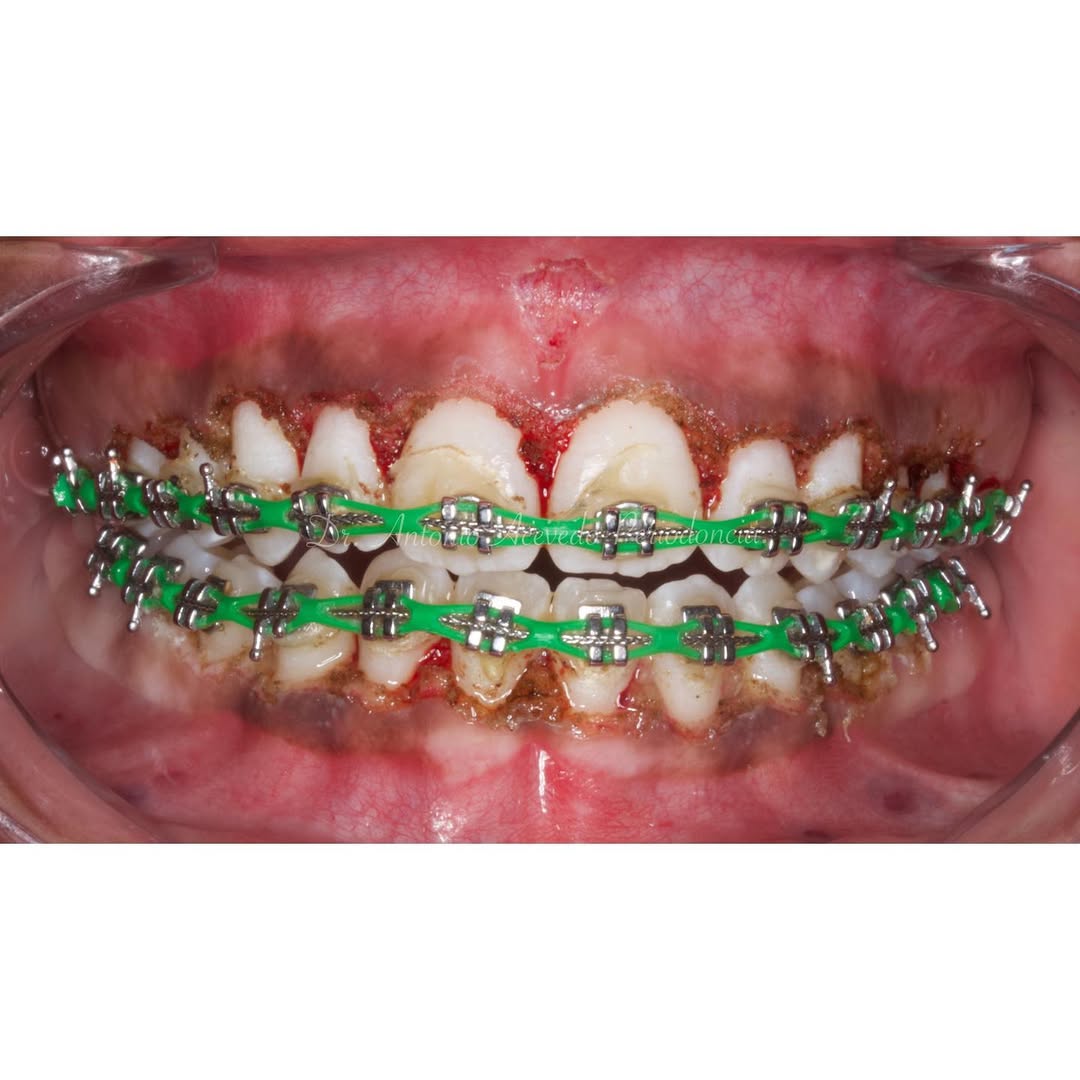

Se presenta un caso clínico de restauración directa en resina composite, ejemplo del valor de la precisión y la técnica meticulosa incluso en procedimientos considerados rutinarios dentro de la práctica diaria. El caso pone en evidencia la importancia del control de la morfología, la textura y la integración cromática, así como del adecuado aislamiento del campo operatorio y la estratificación del material, factores determinantes para conseguir un resultado natural, funcional y duradero. A través de una ejecución cuidadosa, se logró una restauración estéticamente imperceptible y funcionalmente estable, que respeta los principios de mínima invasión y adhesión efectiva. Este tipo de procedimientos, aunque cotidianos, reflejan la constancia y el nivel de exigencia clínica necesarios para ofrecer odontología de calidad en todos los casos, independientemente de su complejidad.